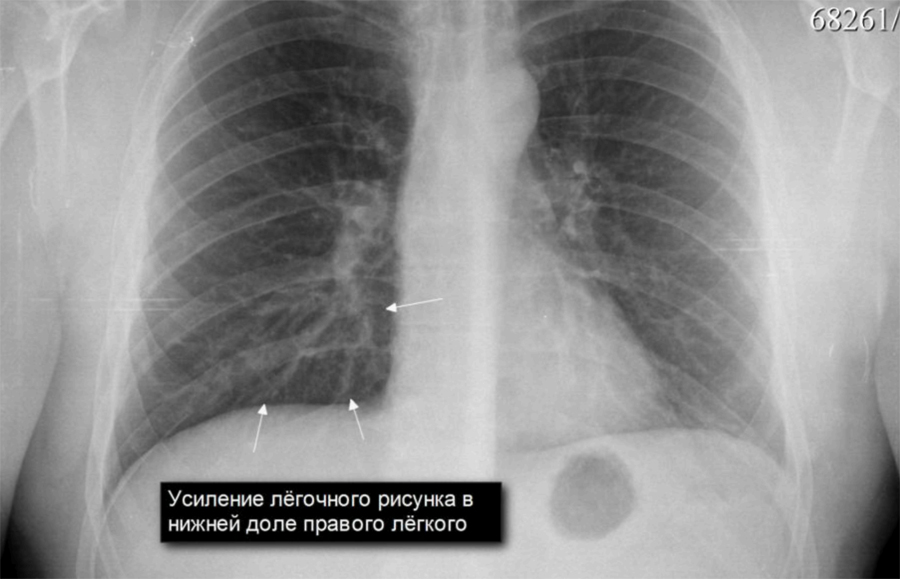

Фотографии, демонстрирующие обнаруженное усиление легочного рисунка

Раздел: Фотодневник открытий